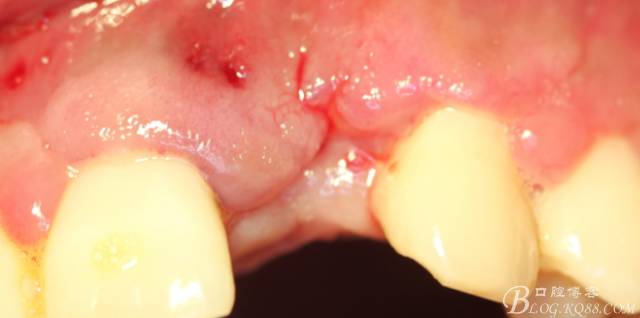

事實證明,我的做法沒有錯誤,一個月后,軟組織健康愈合。鄰牙軟組織沒有退縮。

再次翻瓣。